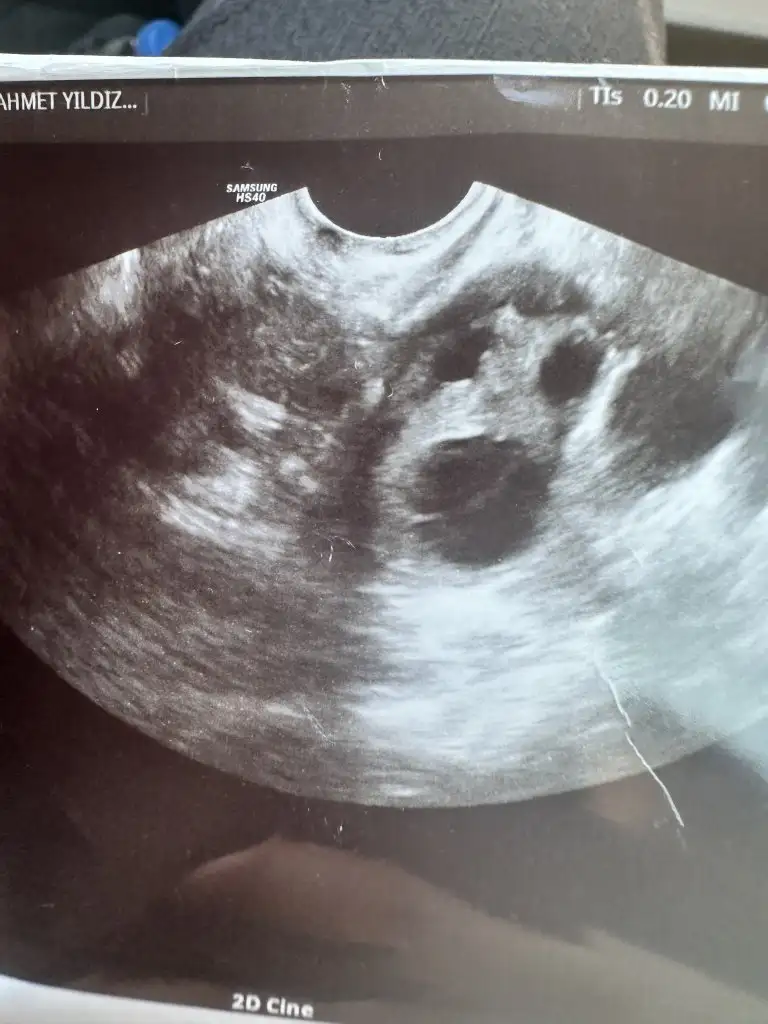

tamam canım at bakalımEvet canım verdi ultrason kağıdı onunda fotografını atayım birazdan ben anlamıyorum yorumlayamadım

Rahmin kalınlaşması iyi canım benimki inceymis doktor ilaç verebilirim dediEvet canım verdi ultrason kağıdı onunda fotografını atayım birazdan ben anlamıyorum yorumlayamadım

Hadi hakkında hayırlısi olsun canm inşallah kandada cikarŞimdi doktordan çıktım canım yumurtan yanlış çatlamış dedi ama rahmin kalınlaşmış dedi kanda bakalım dedi yoksada tedavi verdi çok ilgilendi yumurtam kaliteliymiş sorun yokmuş 2 ay da olması yüksek dedi olmazsa rahim filmi çekeriz dedi moralim düzeldi valla kür falan verdi bana onları yapıcam kan sonucumda saat 16 da çıkacak

İnşallah hamilesindir kuzum benim haberdar et mutlaka biziŞimdi doktordan çıktım canım yumurtan yanlış çatlamış dedi ama rahmin kalınlaşmış dedi kanda bakalım dedi yoksada tedavi verdi çok ilgilendi yumurtam kaliteliymiş sorun yokmuş 2 ay da olması yüksek dedi olmazsa rahim filmi çekeriz dedi moralim düzeldi valla kür falan verdi bana onları yapıcam kan sonucumda saat 16 da çıkacak